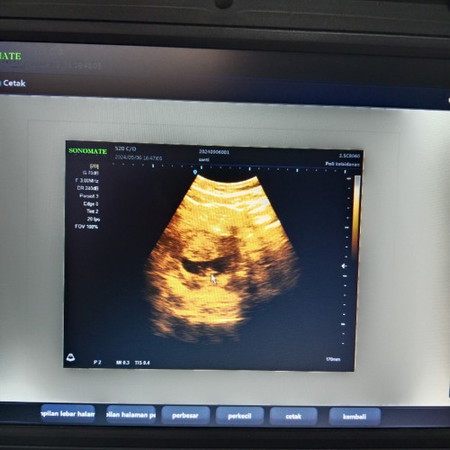

Bun aku habis USG usia kandungan 10 minggu, hasil USG nya baru keliatan kecil janinnya. Ada yg sama?

ya memang kecil bun kalau masih 10 minggu